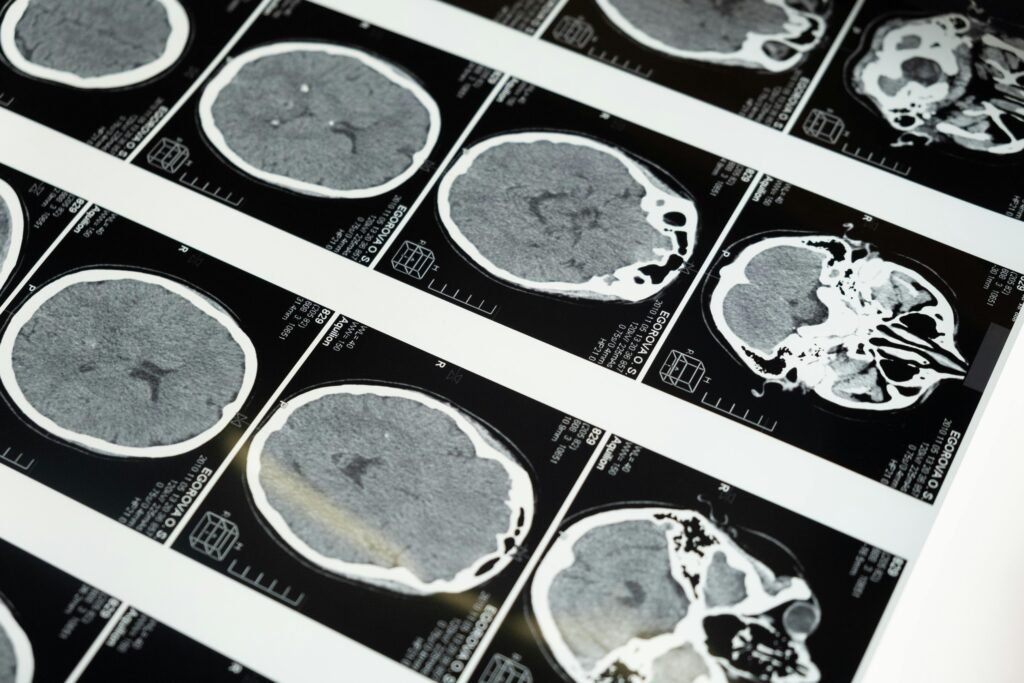

La parálisis cerebral, un trastorno neurológico que afecta el movimiento, el tono muscular y la coordinación, suele tener origen en lesiones cerebrales ocurridas durante el desarrollo fetal, el parto o en los primeros años de vida. Según la Organización Mundial de la Salud (OMS), uno de cada 500 nacimientos puede verse afectado por esta condición, que constituye una de las principales causas de discapacidad motora en la infancia